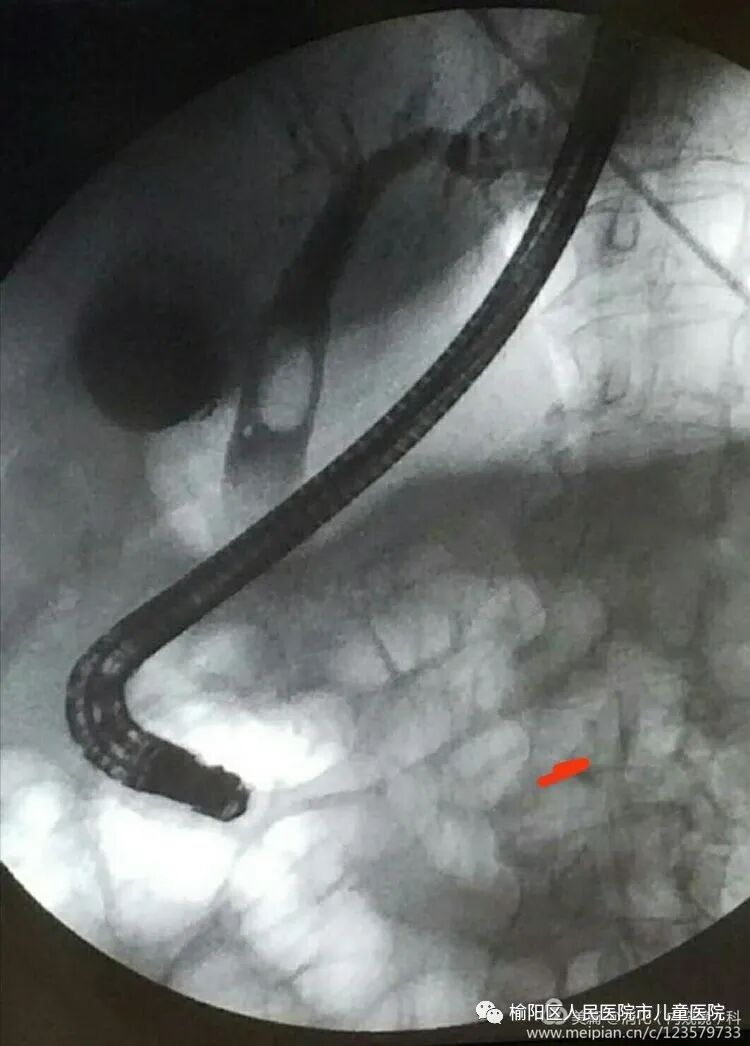

什么是ERCP术?

将十二指肠镜插至十二指肠降部,找到十二指肠乳头,经内镜操作孔道插入一造影导管,并进入十二指肠乳头内,注入造影剂,若胰管及胆管同时显影或先后显影称为ERCP。包括内镜下乳头括约肌切开术、取石术、胆管支架引流术,鼻胆管引流术、胆管支架引流、胆胰管双支架引流、胰管括约肌切开术、胰管取石术、鼻胰管引流术、胰腺假性囊肿引流术等。